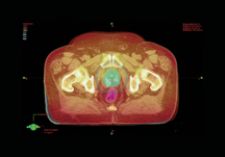

The new generation of OIMS is integrated with EMRs to enable image and data access from anywhere. One of the pioneers of an EMR-integrated OIMS is Varian Medical Systems’ ARIA Oncology Information System, an oncology-specific electronic medical record (EMR) that combines all patient records and makes all administrative, clinical and financial information available to oncologists across the healthcare enterprise. ARIA has an image and plan management application that is DICOM RT-compliant and uses HL7 standards. “For the physicist, when ARIA is integrated with Varian’s Eclipse treatment planning, the need to import and export data between different systems is eliminated, which is important when performing QA and adapting treatment parameters during a course of therapy,” indicated Meryl Ginsberg of Varian Medical Systems. “When physicians can review and edit their patients’ charts at any point in the process, from anywhere in the clinic, they can spend more time with patients and less time with technology.”

One solution that supports IGRT in correctly positioning patients prior to treatment is the MOSAIQ 1.2 by IMPAC. The system features Setup Intelligence, an image-enabled software that employs online or offline quantitative analysis tools for patient positioning. Positional shift information is calculated using MOSAIQ’s planar and 3-D image registration capabilities or can be collected from a third-party system. This information is used in support of clinical decision-making and is integrated with treatment. Being able to review, analyze, record and graph important patient shift data on a daily basis allows physicians to make treatment decisions based on a broader view of the patient’s treatment rather than on a single data point. A new extension to this image-enabled EMR system is the MOSAIQ Oncology PACS, a solution designed to manage increasingly large volumes of image data generated in radiotherapy. The system allows users to archive, retrieve and manage information to support advanced IGRT techniques.

Another critical calculation in treatment planning is staging the tumor. Siemens offers another way for treatment providers to be more efficient through its LANTIS oncology management system. According to Claudia Wasche, product marketing specialist for Siemens Medical Solutions, the new features of the LANTIS include an auto-staging feature, which calculates the stage of the tumor based on TNM values. Wasche explained, “It’s a one click process. It saves time and error.” She added, “Another feature is Careplans for Radiation Oncology. This tool allows one to create a sequence of tasks and procedures which a patient goes through as part of their treatment, (e.g., simulation, planning, treatment, blood count, portal images) — all of them can be planned throughout the course of the treatment. You can, for example, build a template for an IMRT treatment for the breast, and then apply it when needed.” In addition, LANTIS interfaces with all of Siemens' syngo radiation therapy workspaces and thereby enables the integration of treatment data and imaging. LANTIS also interfaces with other linear accelerator manufacturers as well as hospital and information systems, enabling an inter-departmental workflow. In addition, LANTIS provides a central workplace accessible to all users, including the dosimetrist, the therapist, the physicist for performing quality assurance and the oncologist for delivering the dose.